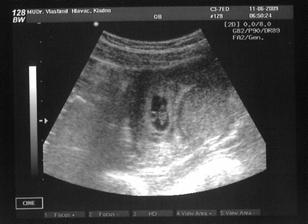

* 11.6.2009: srdce bije, pár blikajících pixelů na obrazovce znamená nový život (pro něj/ni i pro nás)